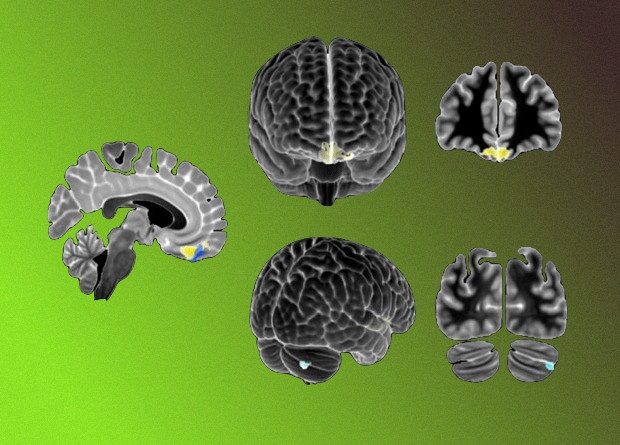

У мышей с расстройством аутистического спектра обнаружили нарушение функциональной связи между медиальной префронтальной корой и мозжечком. Как говорится в статье, опубликованной в Nature Neuroscience, эта связь начинается от коры полушарий и червя мозжечка, идет через ядра мозжечка и вентромедиальный таламус и заканчивается в медиальной префронтальной коре больших полушарий мозга. При активации этого пути мыши проявляли классические симптомы расстройства: меньше взаимодействовали с сородичами и совершали повторяющиеся действия. Напротив, стимуляция нейронов полулунной дольки мозжечка снижала асоциальное поведение, а активация нейронов в задней части червя мозжечка устраняло повторяющееся поведение у самцов мышей. Изменения структур мозга, через которые проходит этот путь, наблюдались и у людей с расстройством аутистического спектра.

Нейрофизиологические основы РАС также до сих пор остаются малоизученными. Ряд исследований указывает на вклад мозжечковой дисфункции в развитие симптомов аутизма у мышей, в том числе из-за делеции гена Tsc1 в клетках Пуркинье. Во многихисследованиях были подробно описаны объемные изменения в задней части червя и в верхней полулунной дольке у детей с РАС; при этом они коррелировали и с тяжестью расстройства.

Питер Цай (Peter T. Tsai) с коллегами из Юго-западного медицинского центра Университета Техаса решили проверить, влияют ли нарушения активности мозжечка на работу медиальной префронтальной коры — участка мозга, который руководит когнитивными функциями у мышей с мутацией гена Tsc1 в клетках Пуркинье. Ученые предположили, что у таких мышей связь между верхней полулунной долькой мозжечка и левой прелимбической областью медиальной префронтальной коры может быть нарушена.